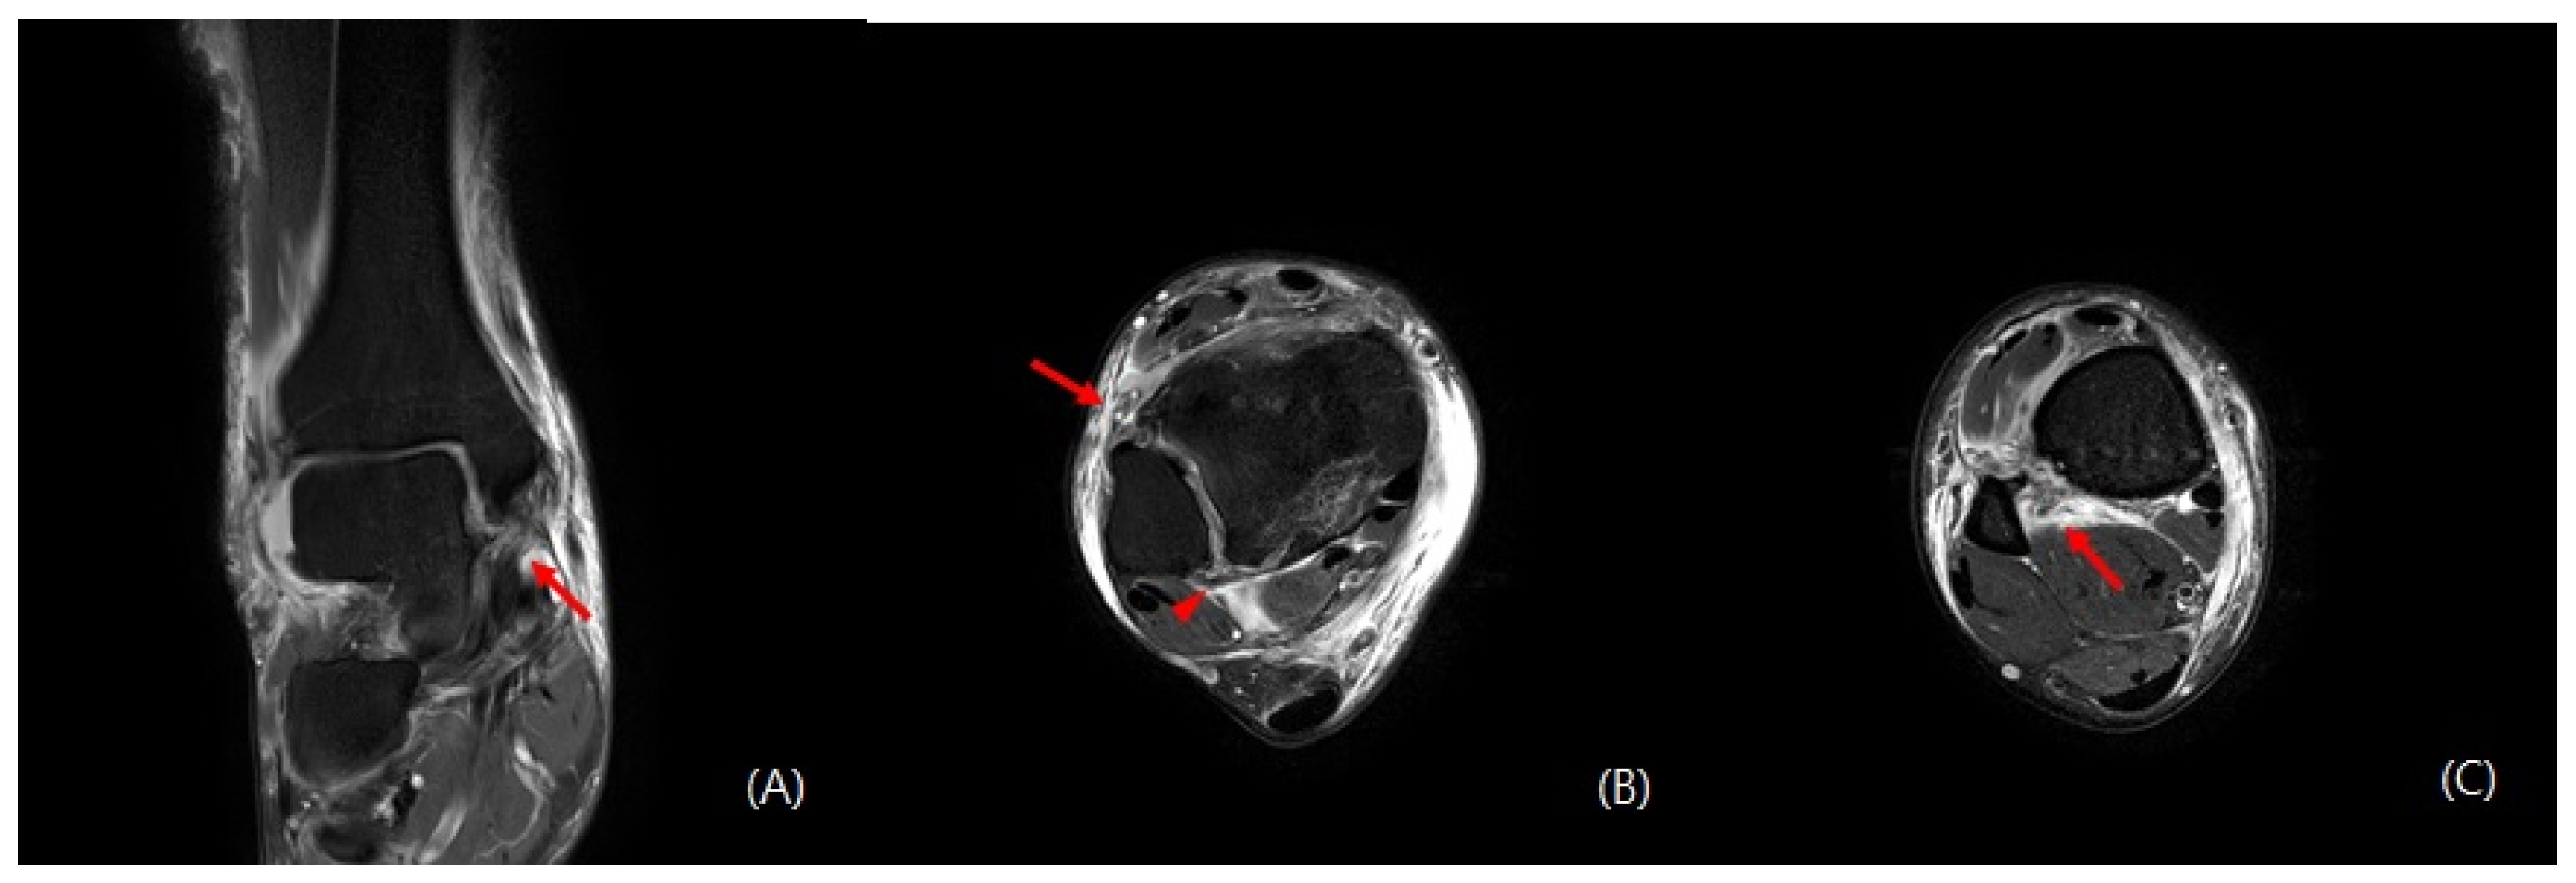

2. Case Presentation